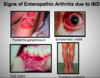

What are spondylarthropathies?

Group of inflammatory conditions that tend to affect the axial skeleton. They all share clinical features of:

- Seronegative (RF -ve)

- HLA-B27 association

- Axial arthritis in spine and SI joints

- Asymmetrical large joint oligoarthritis or monoarthritis

- Enthesitis

- Dactylitis

- Extraarticular features

What conditions are included in spondylarthropathies?

- Ankylosing spondylitis

- Psoriatic arthritis

- Enteropathic arthritis

- Reactive arthritis